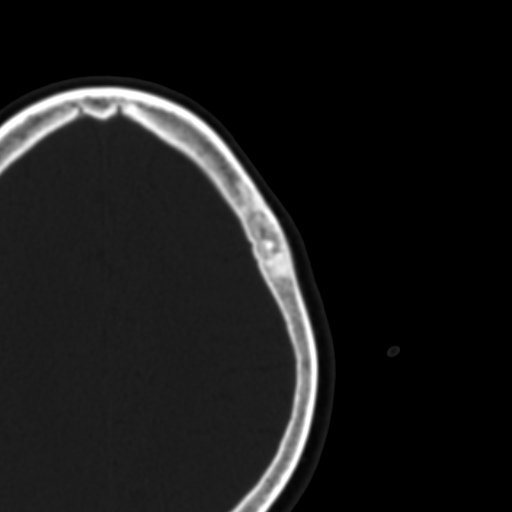

CT51815:颅骨病变

本帖最后由 cefcmj 于 2016-5-28 10:15 编辑 患者女,58岁,因头晕呕吐来做CT检查,检查示脑病未见明显异常;左侧颞骨局限性骨质异常改变,本人认为骨纤维异常增殖症,请 ...

符合颅骨骨纤维异常增殖症表现。

病灶呈膨胀性,并见硬化,未累及内板,支持骨纤诊断。